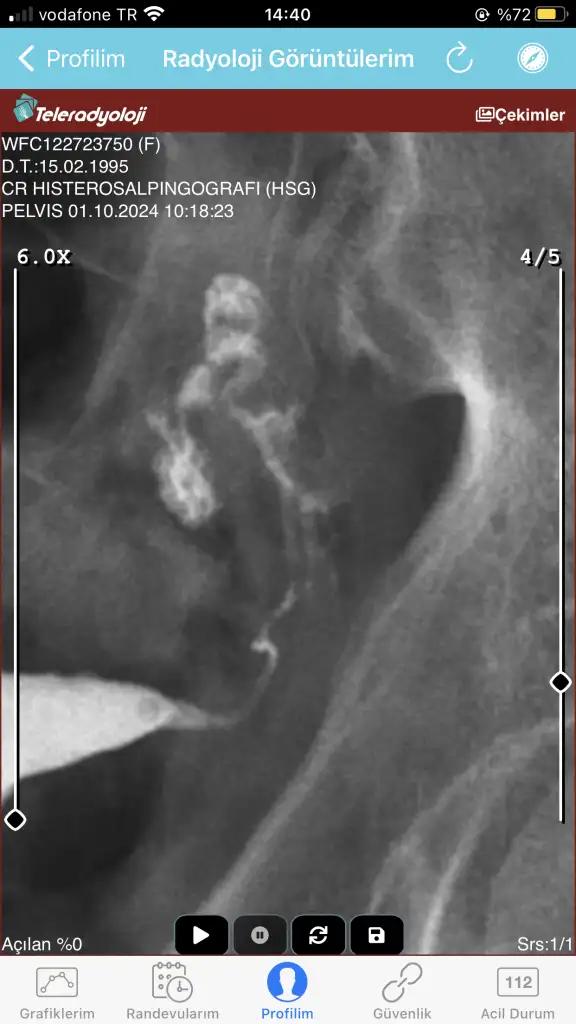

GÖrüntü de önemli. Yani rahimde ilaç doluyenki görüntü.

Görüntüler vardi bem kaldrdimGÖrüntü de önemli. Yani rahimde ilaç doluyenki görüntü.

Canım merhaba , Sağ tüp tam açık sol tüpte zayıf geçiş gözlenmiş yani daralma var sanırım biraz ufak bir yapışıklık olabilir. Her türlü ama gebe kalmana engel değil tek tüple dahi gebe kalınıyor.bugün çekildim doktora göstermedim yardımcı olur musunuz şimdi sağ ve sol tüpüm açık mi

Sol taraf bu canımCanım merhaba , Sağ tüp tam açık sol tüpte zayıf geçiş gözlenmiş yani daralma var sanırım biraz ufak bir yapışıklık olabilir. Her türlü ama gebe kalmana engel değil tek tüple dahi gebe kalınıyor.

Aynen büyük ihtimal yapışıklık var biraz ama en iyisini doktorun bilir tabi önemsiz bir şey de olabilir. Tek tüpünün açık olması yeterli canım zaten. Kafana takılacak bir şey yok bence hiç.Sol taraf bu canım

Benimde hsg raporum bu şekilde sonuçlanmış birşey anlamadımCanım tüplerin açık ama soldan zayıf gitmiş diyor tıkanıklık vs de olabilir ama öyle birşey varsa da bu verilen sıvı ile açılıyor , bu hsgden sonra korunmasız ilişki deneyin mutlaka bundan sonra kalan da çok oluyor , geçmiş olsun

Canım sağ tüpün tıkalı geçiş olmamış doktoruna göster sonucu ne diyecek bakalım endişelenme ama olur muBenimde hsg raporum bu şekilde sonuçlanmış birşey anlamadım

Sol tüpüm açık galiba demiCanım sağ tüpün tıkalı geçiş olmamış doktoruna göster sonucu ne diyecek bakalım endişelenme ama olur mu